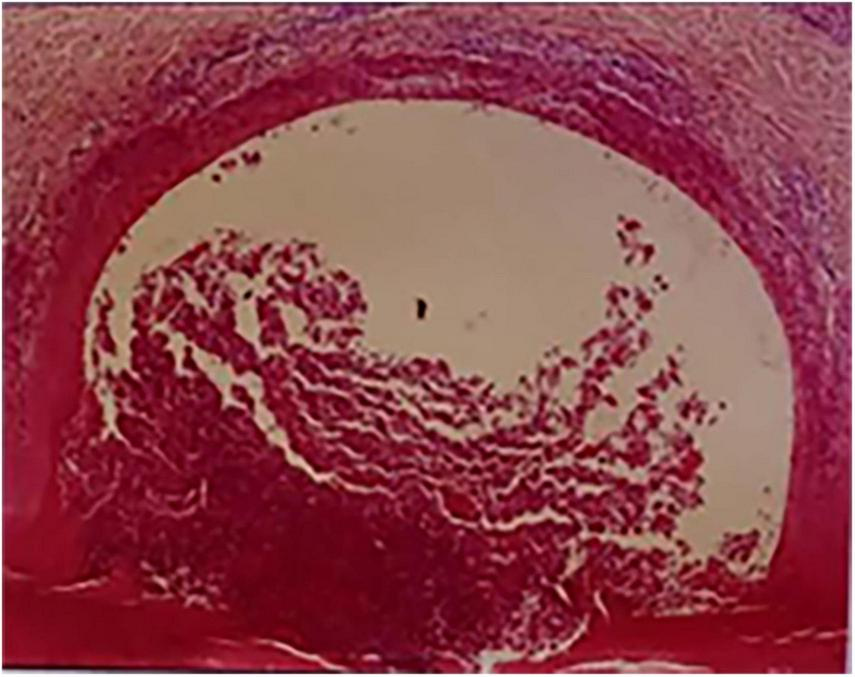

FIGURE 3

The pathological result showed lymphocyte infiltration.

A 52-year-old female patient who had a sex-month history of back pain. The patient took NSAIDs to relieve pain symptoms. However, the patient did not experience significant relief of pain symptoms after taking NSAIDs. More seriously, the patient’s symptoms worsened. The patient failed to walk due to progressive symptoms, and she had to stay in bed due to severe back pain. More treatments were not taken. The patient had difficulty participating in social activities and looking after herself. Therefore, her husband had to take care of her. Eventually, the patient could not tolerate the back pain, and she had to come to our hospital for further treatment. The patient indicated that she had no similar medical history or family history of genetic disorders. The patient also denied the presence of human leukocyte antigen B27 (HLA-B27) in her family history. Physical examination showed back tenderness pain. Palmoplantar pustulosis was observed on the hands and feet (Figures 1A, B). Achilles jerk reflex and knee jerk reflex were normal. The bowel and bladder functions were also normal. Plain radiographs revealed heterogeneous density of some thoracic vertebrae and osteophytes at the edges of some thoracic vertebrae (Figures 2A, B). Thoracic computed tomography (CT) scanning demonstrated cortical erosion, osteophyte, and osteosclerosis of some thoracic vertebrae (Figures 2C, D). The vertebral corner lesion and “kissing” appearance were observed on CT images. Thoracic magnetic resonance imaging (MRI) showed that low signal on T1-weighted images, high signal on T2-weighted images, and high signal on short time of inversion recovery (STIR) images of thoracic vertebrae with vertebral lesions (Figures 2E–I). Sacroiliac joint CT revealed unsmooth joint surface, extensive sclerosis of the bone and patchy low-density shadow (Figure 2J). Multifocal osteoarthritic lesions were found on whole-body bone scintigraphy (WBBS) (Figure 2K). Laboratory examination showed erythrocyte sedimentation rate (ESR) (120 mm/h) and C-reactive protein (10.58 mg/L) were significantly elevated, however, white blood cell count (8.83 × 109/L) and neutrophil percentage (68.8%) were normal. HLA-B27 was positive. No bacteria were found in the bacterial culture. Finally, the patient was diagnosed with SAPHO syndrome based on medical history, clinical symptoms, physical examination, laboratory examination, and radiographic findings. PVP was performed under local anesthesia to treat SAPHO syndrome with vertebral destruction. Puncture needles were placed into the T8 and T9 vertebral body. The puncture location was confirmed with the help of fluoroscopy. Subsequently, the working channel was established. Then, bone cement was slowly injected into the T8 and T9 vertebral body. And the working channel was removed. The pathological result demonstrated that lymphocyte infiltration (Figure 3). Antibiotics were injected intravenously within 24 h after the operation. NSAIDs were administered orally when she felt pain. Post-operative thoracic CT showed that the bone cement in T8 and T9 vertebrae was well dispersed (Figures 4A–C). The patient’s back pain was significantly relieved, post-operatively. On the second day after the surgery, the patient could easily leave the bed and move around. The patient’s symptoms gradually improved during the follow-up period. One year post-operatively, the patient returned to life freely and could participate in social activities. NSAIDs was sometimes taken to relieve pain. Interestingly, the palmoplantar pustulosis on the hands and feet disappeared (Figures 1C, D). Therefore, the patient was satisfied with the treatment.